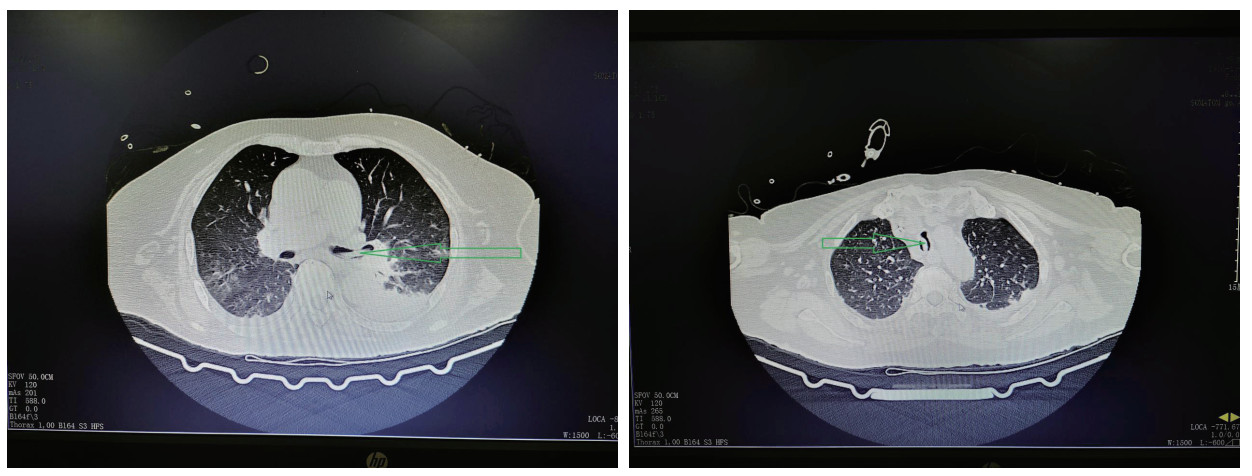

患者有明确高温暴露史,根据患者病史,查体及相关辅助检查,诊断“经典型热射病、Ⅰ型呼吸衰竭、支气管扩张伴感染、急性肾损伤”,继续予气管插管,呼吸机辅助呼吸,并每日监测气管插管气囊压力,迅速物理降温,抗感染,抗凝,补液扩容改善循环等对症治疗,经积极治疗后患者呼吸,循环等各项生命体征趋于稳定。患者白细胞明显高于正常值,且淋巴细胞占比明显增高,行骨髓穿刺活检后血液科专科会诊,诊断为“慢性淋巴细胞白血病,骨髓增殖性疾病”。患者住院2 d后开始出现阵发性呼吸困难,发作时伴大汗淋漓,夜间尤为明显,持续数分钟到数十分钟不等,症状发作时经皮血氧饱和度下降至90%,潮气量由约400 mL下降至约300 mL,两肺听诊可闻及少许哮鸣音,患者既往有慢性支气管炎病史,考虑支气管哮喘发作引起气道痉挛,应用甲基强的松龙针40 mg静脉注射,调整呼吸机参数,后患者呼吸急促逐渐缓解。入院第3天复查胸部CT(见图 2):“两肺感染性病变,右肺中叶、左肺上叶部分支扩伴感染,两侧胸腔少量积液伴邻近两肺下叶膨胀不全,气管及左侧支气管内条状高密度影”。根据胸部CT结果,气管及左侧支气管内高密度影考虑气道内痰液阻塞,加强翻身拍背,吸痰等对症治疗。入院第4天凌晨,患者再次出现呼吸急促,大汗淋漓,两肺听诊可闻及少许哮鸣音,经皮血氧饱和度下降至83%,潮气量明显下降至200 mL左右,血气分析提示:“PaO2:48 mmHg,PaCO2:30.5 mmHg,SatO2:83%,BE:-5 mmol/L,AB:18.5 mmol/L”。继续糖皮质激素应用缓解气道痉挛,鼓肺吸痰,上调呼吸机参数等综合治疗,0.5 h后患者氧合无明显改善,不排除气道梗阻可能,立即行床边纤维支气管镜检查,镜下见气管及左主支气管内有2条奶油色活动性虫体,给予夹出,夹出虫体后患者呼吸逐渐平稳,氧合明显改善(支气管镜下虫体图片详见图 3)。2条虫体为活虫,放置在生理盐水中可见活动,测量虫体长度约25 cm,虫体直径约5 mm(虫体全图详见图 4),经本院感染科及市疾控中心会诊后认定2条虫体为蛔虫成虫,故此,患者诊断“蛔虫病”明确,治疗上予阿苯达唑片400 mg/d鼻饲, 连续服用2日,驱虫治疗后5 d内大便中总共排出蛔虫成虫12条,驱虫治疗效果显著,病情好转。

| 图 2 入院后3 d,胸部CT示气管及左侧支气管内异物(绿色箭头所指为蛔虫虫体) |